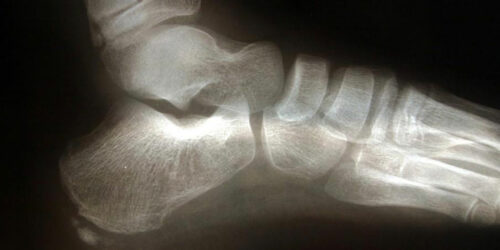

Commonly affecting athletes who frequent activities include running and jumping, heel spur is caused due to calcium deposits on the underside of the heel bone. The symptoms include inflammation of tissues and tendons near the spur, pain while walking or jogging, formation of calluses, swelling or redness of the affected part of the heel.